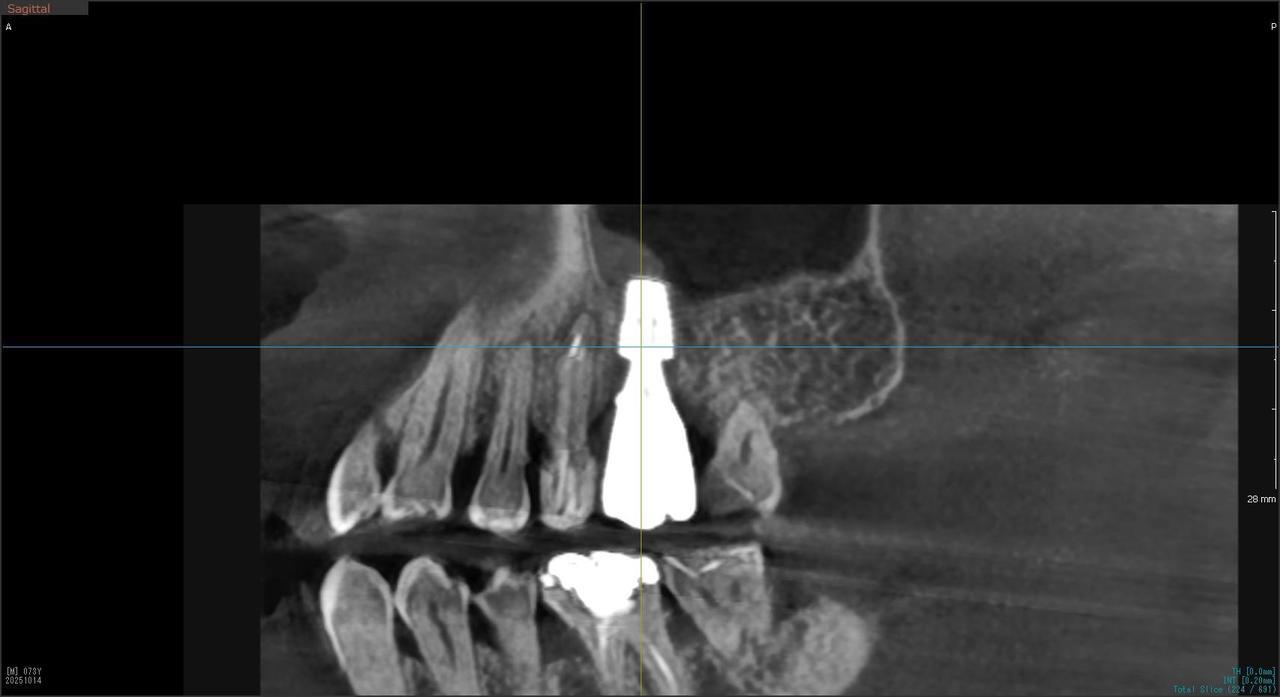

4.右上5が折れたために、インプラント抜歯即時埋入をおこなったインプラント治療のケース。

T・T 様 女性 40代

症状としては、 右上5番の歯が折れてしまった。保存することは不可能な状態であった

治療法としては、患者様は、歯が折れたことを主訴に来院。インプラント治療を希望したため、抜歯した当日に、インプラント埋入をおこなって、骨欠損部には人工骨を補填した。1か月半後にインプラントが骨と結合していることを確認できたため、光学印象を行い、2か月後に、最終補綴物として、アバットメントとジルコニアクラウンの装着を行いました。

治療結果としては、抜歯したと同時にインプラントを埋入することで、抜歯した穴が自然に治る過程で、インプラントの骨結合と組織の治癒が同時に行われるために、2か月という治療期間で治療を終了することができたことと、機能面・審美面でも回復を行うができた。

治療の期間・回数:約2か月、インプラント抜歯即時埋入から最終補綴物装着まで4回

治療の価格:352,000円(税込)

治療費の内訳:インプラント基本料(フィックスチャー及び手術費用、投薬費用、レントゲン費用、インプラント上部費用(アバットメントおよびジルコニアクラウンの費用用)330000円(税込み)。オプション、抜歯即時埋入加算(人工骨費用を含む) 22000円(税込み)

治療のリスクや副作用:手術後に、痛みや腫れ、出血、合併症などを引き起こす可能性があります。噛む感覚がご自身の歯と異なる場合があります。見た目がご自身の歯と異なる場合があります。手術後にメインテナンスを継続しないと、インプラントが抜け落ちる可能性があります。